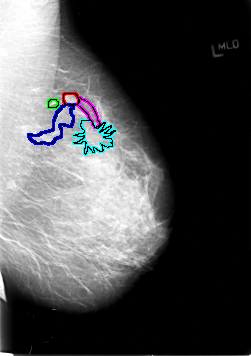

FILE: B_3029_1.LEFT_MLO.OVERLAY

TOTAL_ABNORMALITIES 5

ABNORMALITY 1

LESION_TYPE MASS SHAPE ROUND MARGINS CIRCUMSCRIBED

ASSESSMENT 3

SUBTLETY 3

PATHOLOGY BENIGN

TOTAL_OUTLINES 1

BOUNDARY

ABNORMALITY 2

LESION_TYPE CALCIFICATION TYPE PLEOMORPHIC DISTRIBUTION LINEAR-SEGMENTAL

ASSESSMENT 4

PATHOLOGY MALIGNANT

ABNORMALITY 3

ABNORMALITY 4

LESION_TYPE MASS SHAPE ARCHITECTURAL_DISTORTION MARGINS N/A

SUBTLETY 2

ABNORMALITY 5